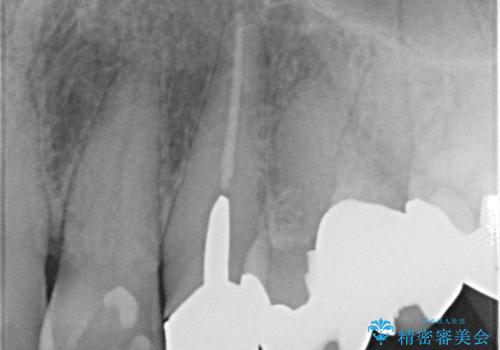

また、左上の犬歯の根の再治療も行いました。

- ジルコニアクラウンスタンダード・仮歯 13.2万円×6 左上3精密根管治療(リトリートメント)・ファイバーコア 12.1万円費用は治療当時の料金となります